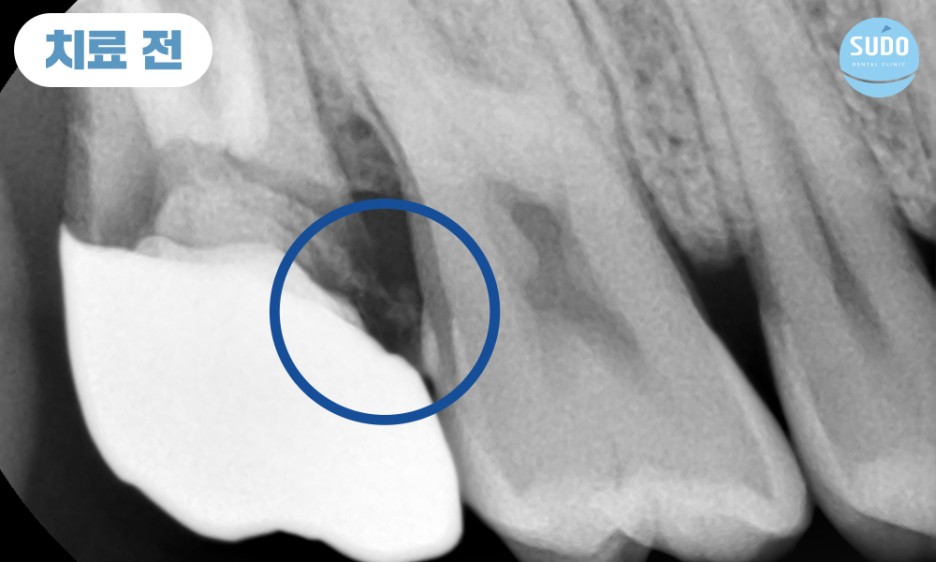

위 환자분은 20대 후반의 남성분으로, 오른쪽 위 가장 안쪽 어금니 보철물이 빠질 것 같다고 하시며 수도치과로 내원해 주셨습니다. 보철물이 완전히 부러진 상태는 아니라서 기존 보철물을 제거한 후 치아 내부 상태를 확인하였습니다.

상태가 양호하다면 부족한 부분을 보강하기 위해 기둥을 세우고 재보철치료를 진행할 수 있었으나, 내부 상태가 좋지 않을 경우 치아를 발치하고 임플란트 치료를 진행해야 할 것으로 설명드렸습니다.

기존의 보철물 제거하고 보니, 이미 뿌리까지 충치가 많이 진행된 상태로 살려서 쓰기 힘들 것이라 판단되어 당일 발치 후 임플란트 진행 계획을 수립하였습니다.

이전 진료 당시에 신경치료를 완료한 후 보철물을 부착한 상태였으므로 충치가 심하게 진행되었음에도 통증을 전혀 느낄 수 없었습니다.